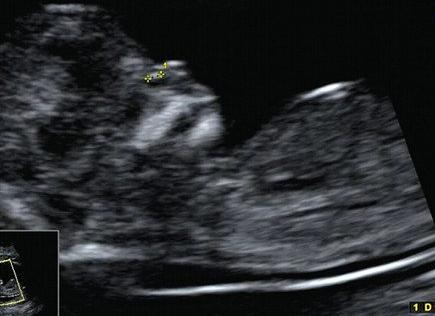

Плодное яйцо без эмбриона часто довольно диагностируется в матке даже у совсем здоровых и молодых женщин. Какова причина данной лечится, патологии ли это, как избежать такого замершей рода беременности?